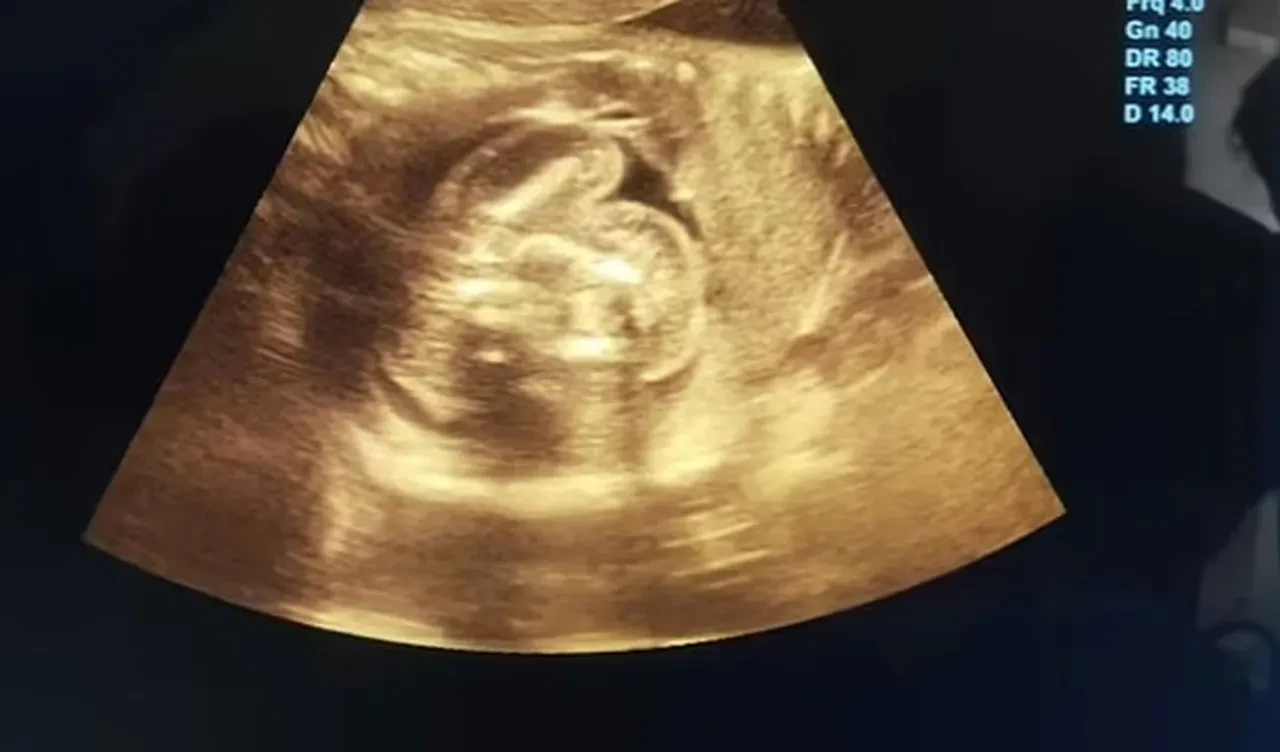

Hindistan'da yaşayan 32 yaşındaki, 35 haftalık hamile bir kadın rutin kontrolü için doktora gitti. Erkek bir bebeğe hamile olan kadının ultrason taraması sırasında doktor, ilginç bir durum olduğunu söyledi. Daha önceki taramaları normal çıkan kadının, doğmamış bebeğinin karnında 'kemik içeren ek bir yapı' keşfedildi. Doktor, iki cismin fetüs olduğunu söylediğinde ise herkes büyük bir şaşkınlık yaşadı.

Uzmanlar, fetüslerin hayatta kalamayacak kadar az gelişmiş olduğunu ifade ettiler. Taramayı gerçekleştiren Dr. Prasad Agarwal, yerel medyaya yaptığı açıklamada , "Bu bebekte çok sıra dışı bir şey fark edecek kadar şanslı ve dikkatliydim; birkaç kemiği ve karnında fetüs benzeri bir yapı bulunduğunu anladım. Bunun normal olmadığını fark ettim. Bu, dünyadaki en nadir vakalardan biri olan 'fetüs içinde fetüs' idi.'' dedi.